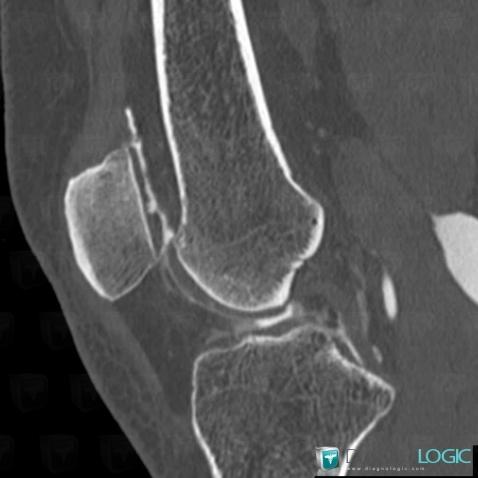

Degenerative joint disease, Femorotibial joints - Intercondylar notch, CT

Here is the specific information in the key image above:

- Diagnosis Degenerative joint disease, Location(s) Femorotibial joints - Intercondylar notch, with gamuts